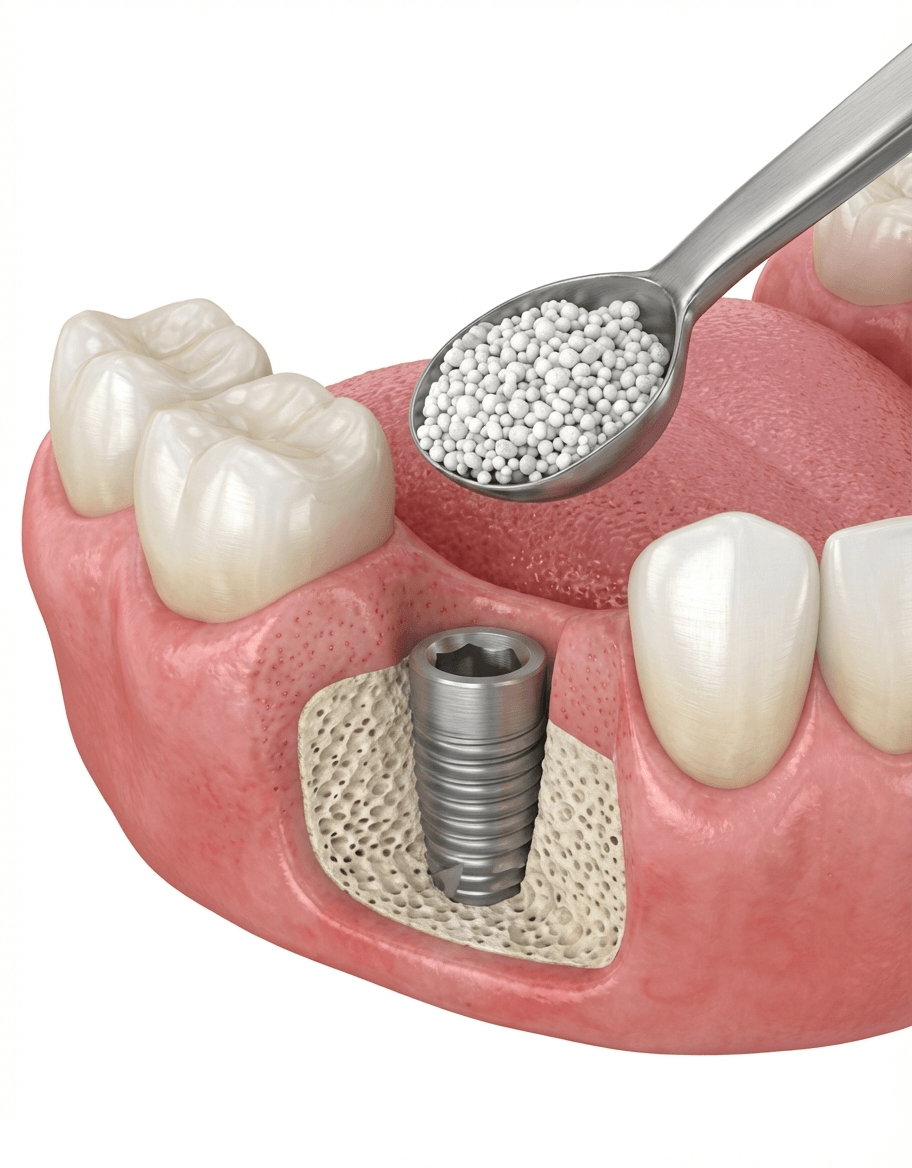

≫ 当院の「骨造成」について

サイナスリフト

サイナスリフト(上顎洞底挙上術)は、歯科インプラント治療において上顎の骨の高さが大きく不足している場合に行われる骨造成手術の一つです。

上顎洞(鼻の横にある空洞)の底部に、歯茎の横側からアプローチし、上顎洞の粘膜(シュナイダー膜)を持ち上げ、できたスペースに自家骨や人工骨などの骨補填材を挿入します。そのため、骨の高さが極端に足りないケースや、複数の歯をまとめてインプラント治療する場合に有効です。一般的に補填した骨がしっかりと定着するまでに個人差がありますが、数ヶ月程度の待機期間が必要となるため、全体の治療期間が長くなります。当院では、CT上でのプランニングに加えて上顎骨の3Dモデルを作成し、事前シュミレーションを行い、手術の安全性をより高めています。

ソケットリフト

歯科インプラントにおけるソケットリフトは、上顎の奥歯のインプラント治療で、骨の高さがわずかに不足している場合に適用される骨造成術の一つです。上顎の奥歯の上にある上顎洞の底にある膜を、インプラントを埋入するために開けた穴から特殊な器具で少しだけ押し上げ、できたスペースに骨補填材を入れて骨の高さを増やす方法です。インプラントを埋入するために開ける穴(歯があった部分)からアプローチするため、歯肉を大きく切開する必要がないのが大きな特徴です。歯肉の切開が小さく、手術範囲が狭いため、術後の痛みや腫れが比較的少ない傾向にあり、治療期間や通院回数を少なくできます。骨の不足量が大きい場合や、骨の高さが不十分な場合には適用できず、サイナスリフトが必要となります。

ご自身の骨の状態がソケットリフトの適応になるかどうかは、CT検査などによる詳細な診断が必要です。

GBR法・ソケットリフト・サイナスリフト

骨が少ない方への対応。骨誘導再生や骨移植により、インプラント埋入を可能にします。